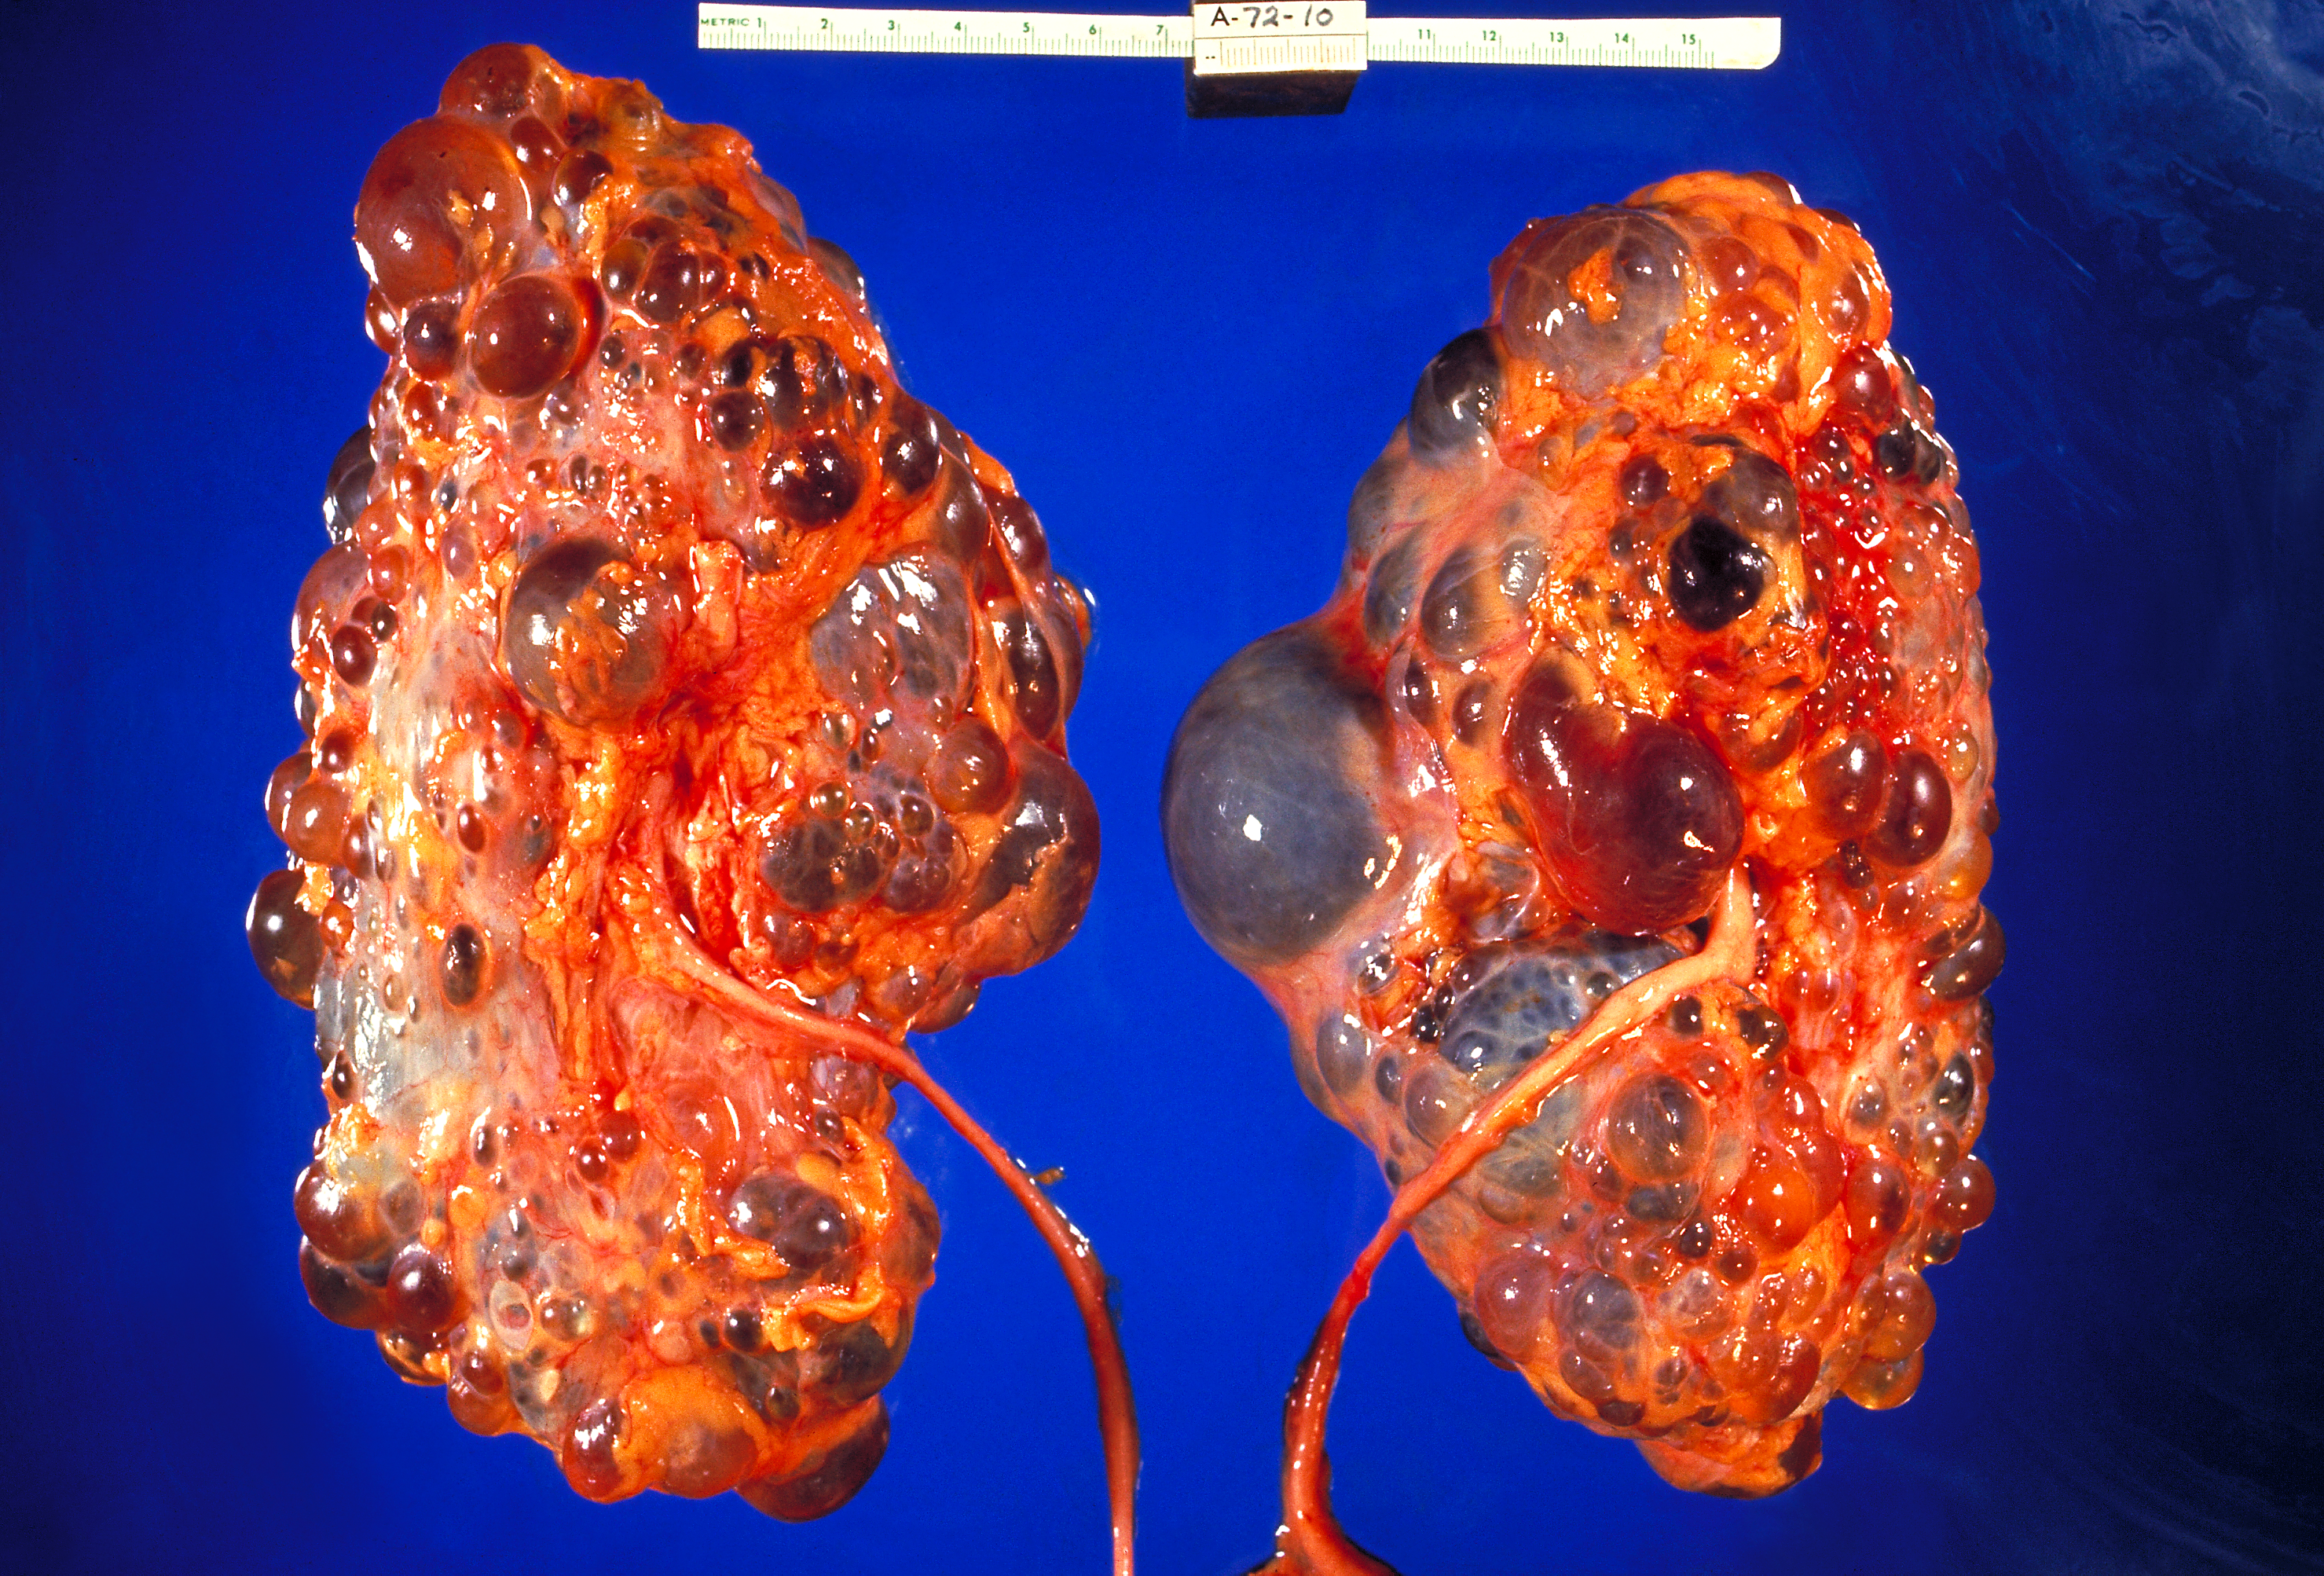

신장 병리학은 신장 질환의 진단 및 특성 규명을 다루는 해부 병리학의 하위 전문 분야이다. 의료 환경에서 신장 병리학자는 일반적으로 경피적 신장 생검을 통해 진단 검체를 얻는 신장내과 전문의 및 장기 이식 외과 의사와 긴밀히 협력한다. 신장 병리학자는 전통적인 현미경 조직학, 전자 현미경 및 면역 형광 검사 결과를 종합하여 최종 진단을 내려야 한다. 의학적 신장 질환은 사구체, 세뇨관 및 간질, 혈관 또는 이러한 구획의 조합에 영향을 미칠 수 있다.